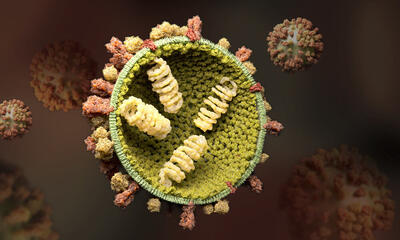

موردی از پشه آئدس در فارس مشاهده نشده است - تسنیم

معاون بهداشت دانشگاه علوم پزشکی شیراز، گفت: تاکنون موردی از انتقال محلی و صید پشه آئدس در استان فارس گزارش نشده است.